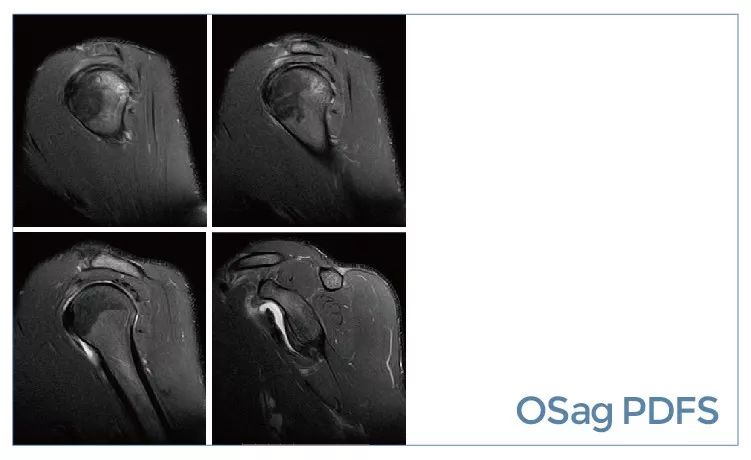

【朗润影像档案】磁共振影像病例分享(编号20190927)